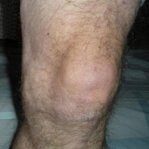

Gonfiore e infiammazione dell'articolazione del ginocchio sono un segnale d'allarme di gravi patologie. Senza trattamento, possono portare alla completa perdita di mobilità e alla necessità di un intervento chirurgico. Agisci immediatamente ai primi sintomi!